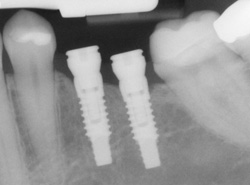

- Computer-Enhanced Treatment Planning: We have special software on our computer that allows us to evaluate your dental CT scan in three dimensions for bone quality, bone quantity, and bone location, enabling the best possible placement of your dental implants. This also allows us to work closely and smoothly with your restorative dentist to ensure an ideal result where your dental implants are concerned.

Implants are versatile. If you are only missing one tooth, one implant plus one replacement tooth will do the trick. If you are missing several teeth in a row, a few strategically placed implants can support a permanent bridge (a set of replacement teeth). Similarly, if you have lost all of your teeth, a full bridge or full denture can be permanently fixed in your mouth with a strategic number of implants.